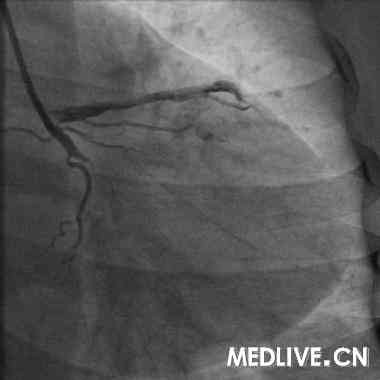

经右股动脉途径,6F,JR4.0引导管,HT BMW Universal引导丝顺利通过右冠闭塞病变部位,Diver血栓抽吸导管于病变部位及其近、远段部位连续抽吸,反复5次,造影可见右冠血流恢复,余狭窄最重部位直接植入Excel支架3.5*14mm,12atm释放,16atm原位后扩张,最重效果满意,右冠TIMI血流3级(图5-7)。

急诊右冠介入治疗成功(图12);择期回旋支的介入治疗成功(图11)。